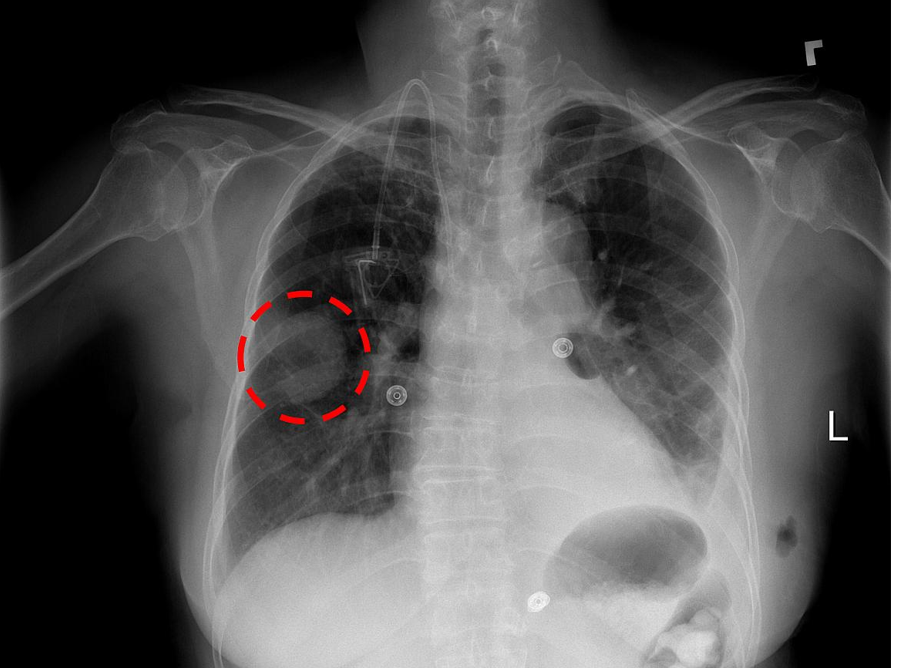

NIH Image Gallery / Flickr - Chest x-ray showing a lung mass - https://www.flickr.com/photos/nihgov/37136227250/in/photolist-YzASyb

Pictures could have power over people when it comes to tackling risky health habits like smoking, dodgy diets, or lounging too long on the couch. Combined analysis of 21 studies concludes that if a patient views their own medical imaging such as ultrasound or radiography results - to see for themselves their personal disease risk - that may discourage risky actions more than non-visual communication. Existing studies have drawbacks, though, so the authors want to see more research to confirm the potential of feeding back medical images to patients.

They say a picture can convey a thousand words, and researchers have found that using medical imaging technologies that can visualize health may discourage risk-related behaviors more than non-visual information. The meta-analysis, publishing March 3rd in the open access journal PLOS Medicine, finds that when individuals undergo an imaging procedure and are shown visual personalized information about their own risk of disease, they may be more likely to reduce risky behaviors.

Gareth Hollands and colleagues at the University of Cambridge, UK conducted a meta-analysis of 21 randomized controlled trials involving over 9,000 adult participants. Participants were either shown visual examples of personalized risk information following an imaging procedure, such as computed tomography, ultrasound, or radiography, in addition to health information or advice, or they received health information or advice with no visual feedback. The trials reported on behaviors including smoking, medication use, physical activity, diet, oral hygiene, sun protection, tanning booth use, blood glucose testing, skin self-examination, and foot care.